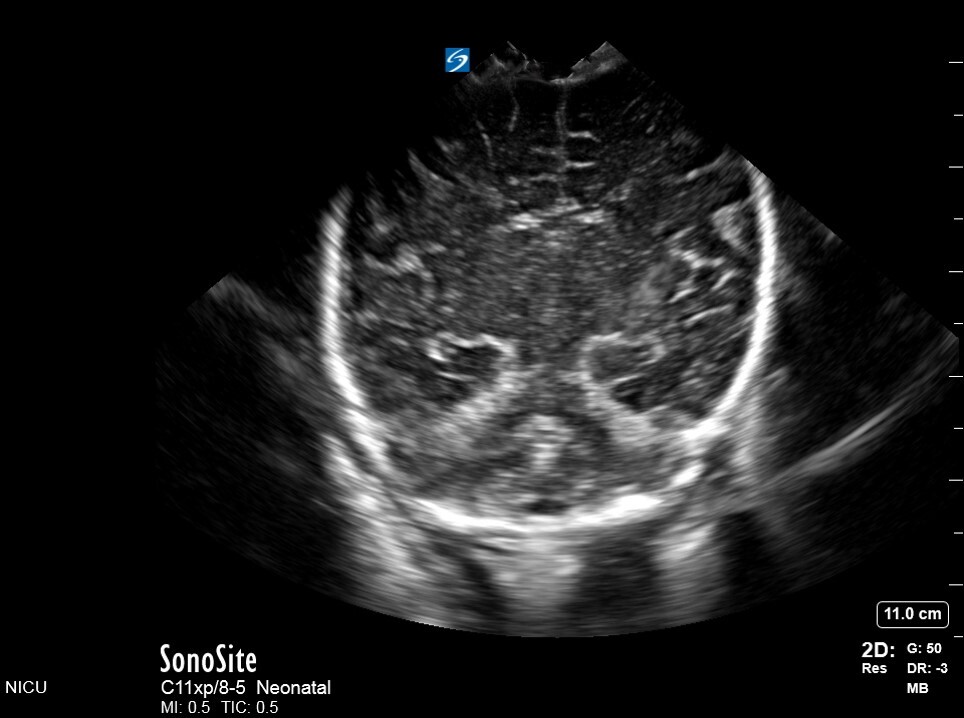

Neonatology C4 1 Image